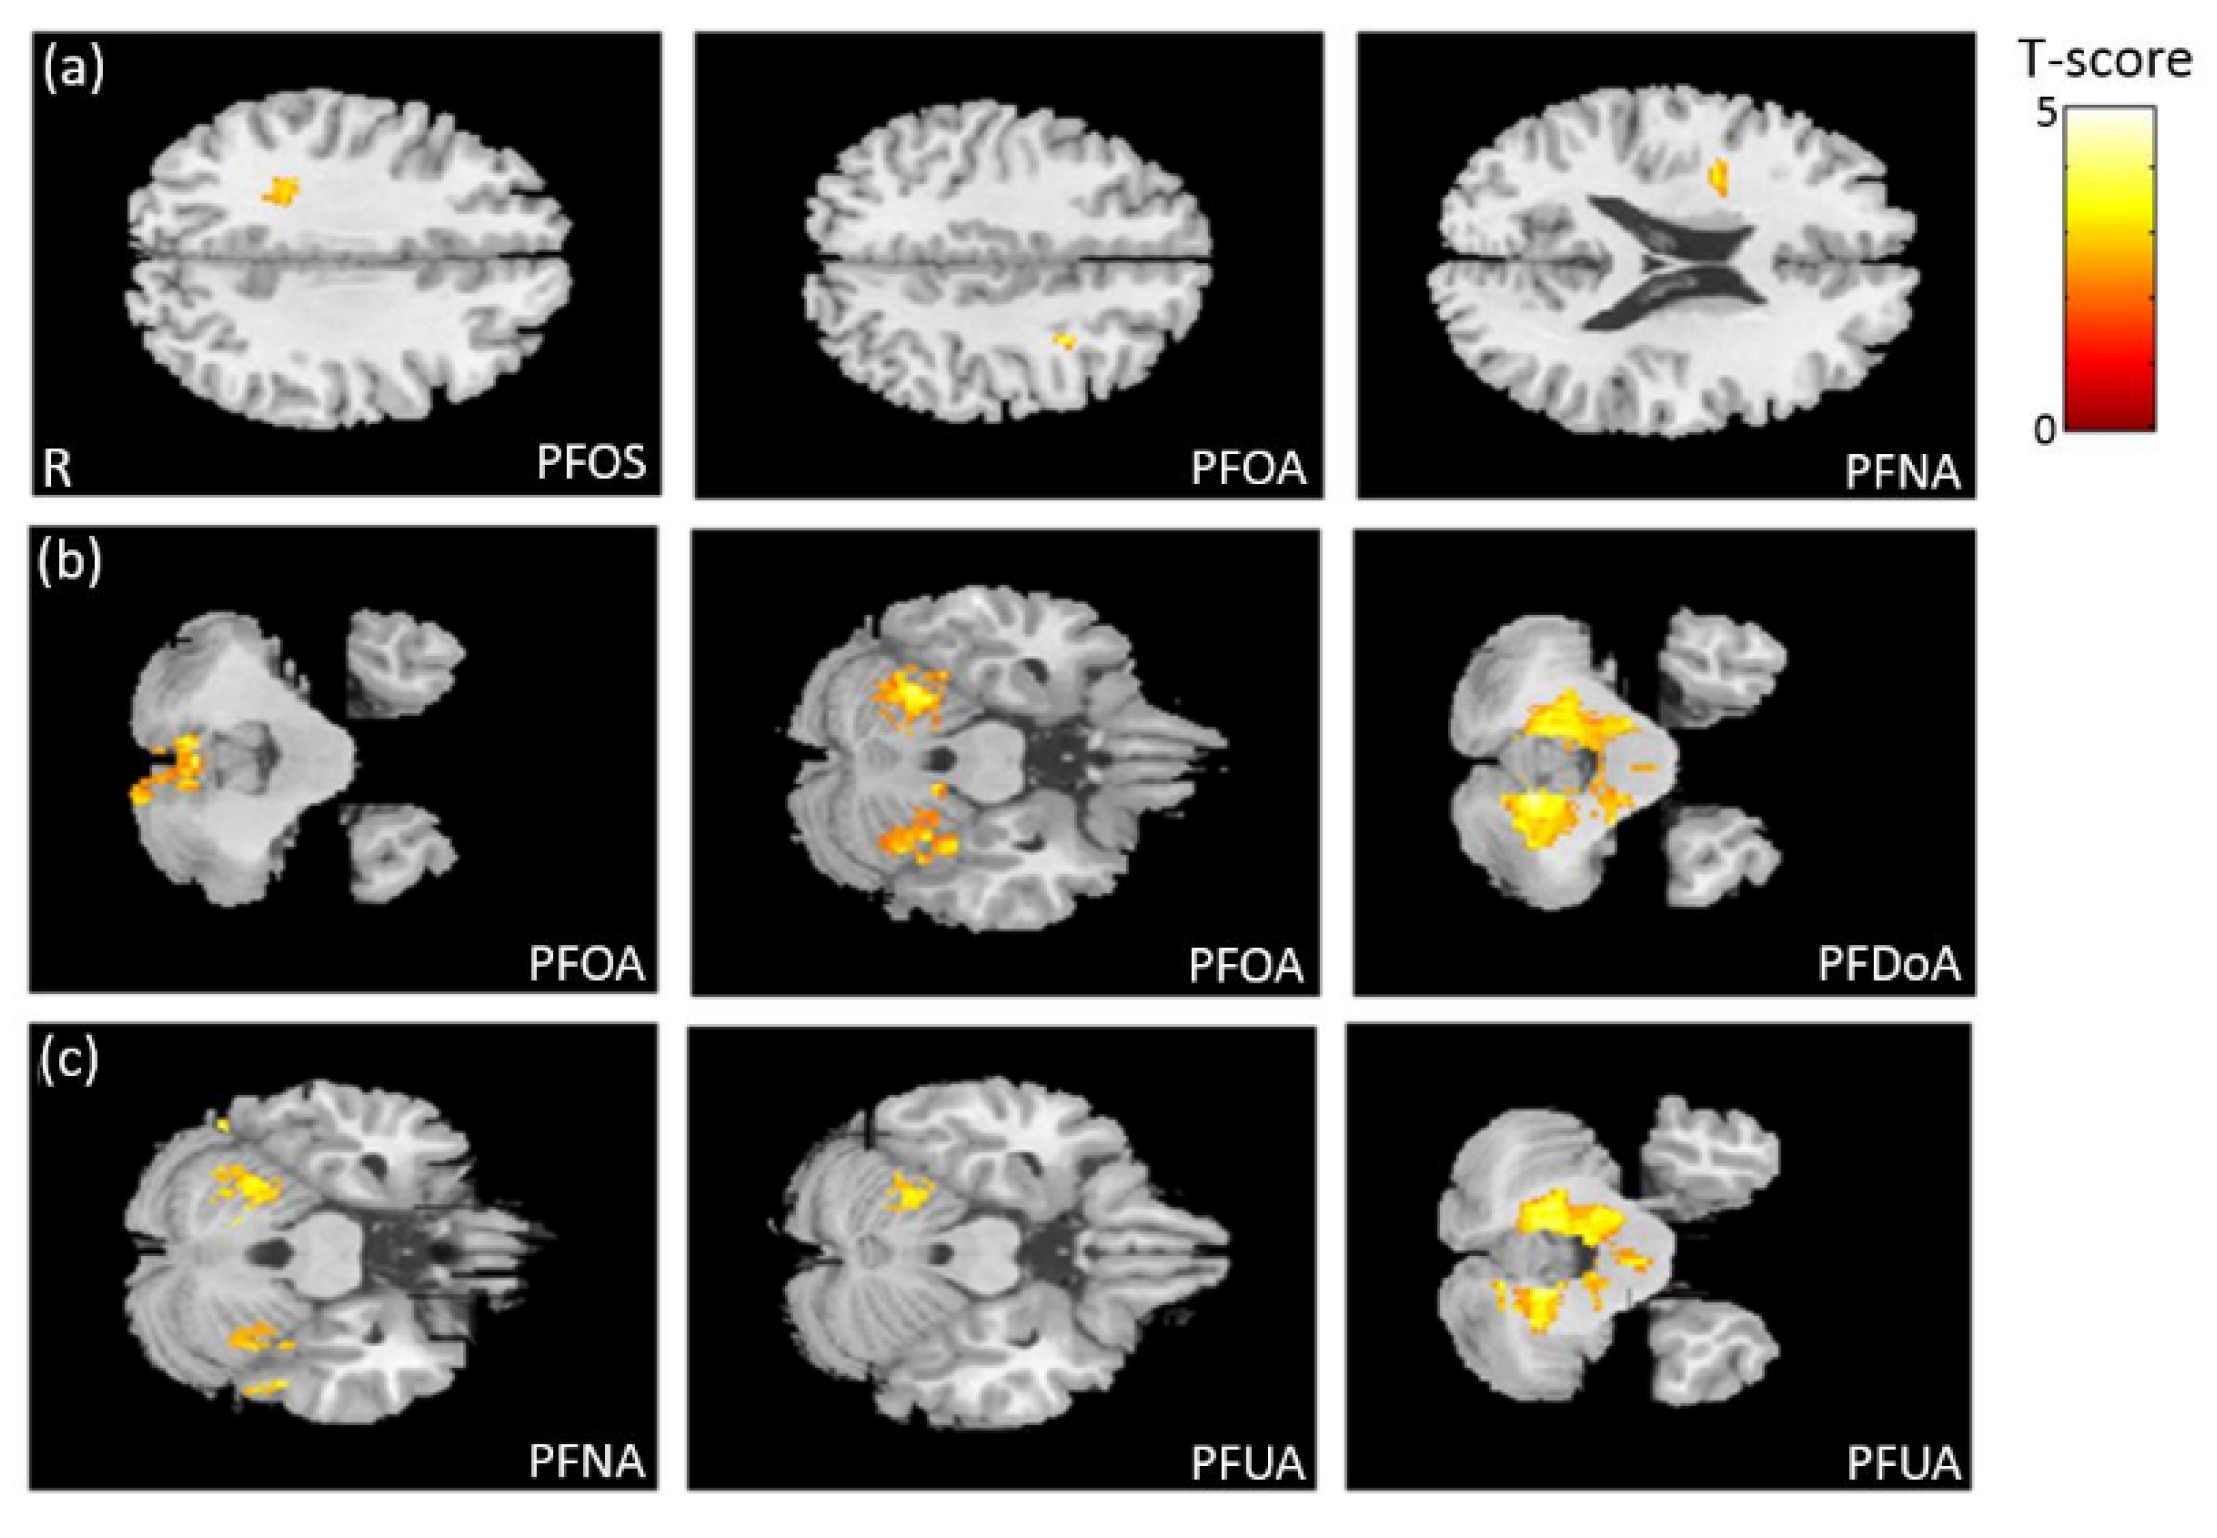

3.3. The Association between PFCs and VBM

3.6. The Association between PFCs and GQI

4.2. Brain Volume and White Matter Structure Associated with PFCs